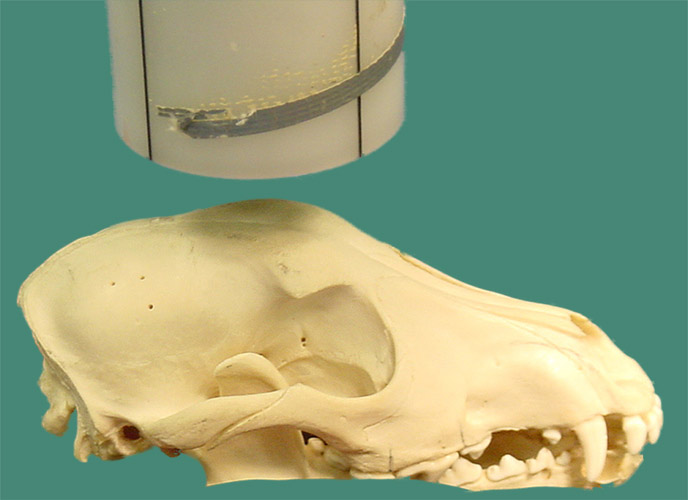

Left-Right Lateral or Right-Left Lateral

The patient is in lateral recumbency and the rostral aspect of

the head is raised, to create a parallel relationship with the film.

This technique is often used for routine surveys, but the diagnostic

ability of this technique is limited by superimposition of structures.

The open mouth view prevents overlay of the coronoid processes of

the mandibles.